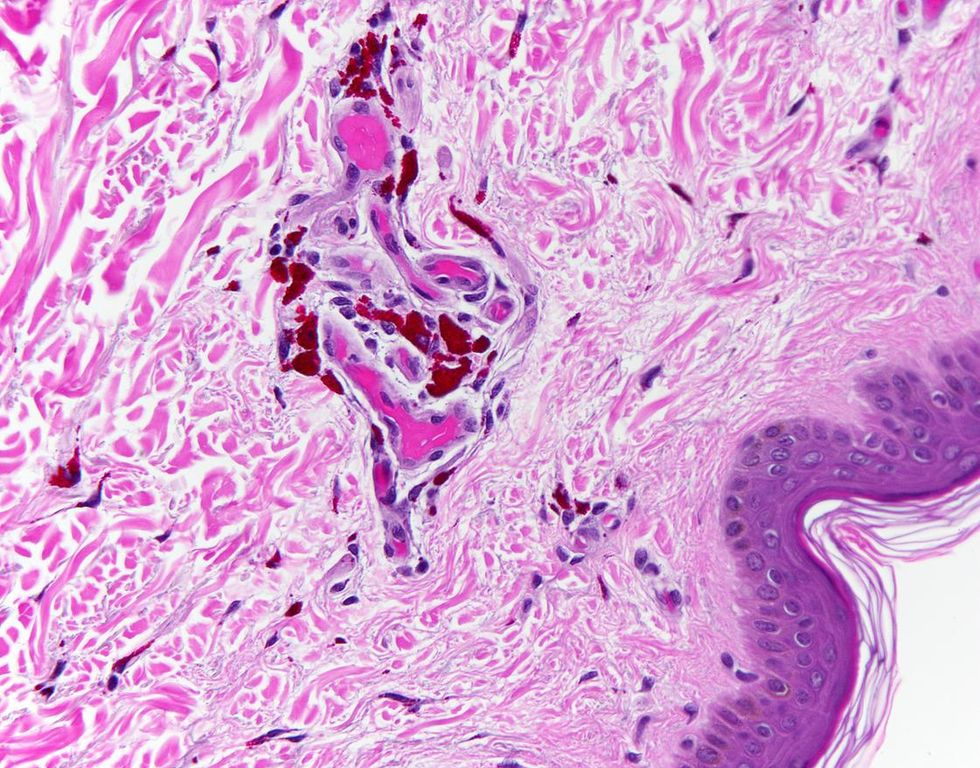

Birefringence

The majority of the images are representative of what Dr Hamel sees when performing autopsies. The colours are diagnostic colours which are added to slides to help define human tissue.